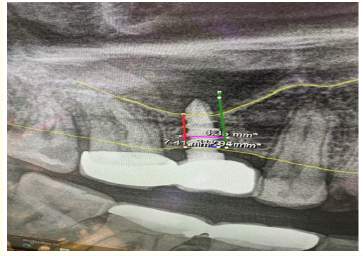

Pre and Postoperative Change in Dentin Thickness of Danger Zone in Mandibular 1st and 2nd Molars: A Cross-Sectional CBCT Study

Tariq Muhammed Aqili, Abdulmajeed Abdulaziz Baik, Abdulbari Saleh Aljohani and Muhannad Mohammed Hakeem. 22(7): 79-87.